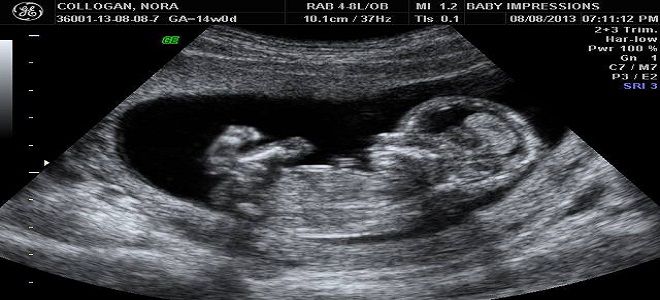

На 19-й неделе беременности развитие ребенка идет стремительными темпами. В центральной нервной системе происходят важные изменения: формируются связи между нейронами, увеличивается объем головного мозга. Это приводит к усложнению рефлекторных реакций и росту двигательной активности плода: он активно шевелит руками и ногами, а также сосет свой большой палец. Эти процессы подтверждаются результатами ультразвукового исследования.

Важно отметить, что рост и вес плода являются индивидуальными характеристиками его развития. Однако во время ультразвукового исследования специалисты обращают внимание на эти параметры, сравнивая размеры ребенка с предполагаемым сроком беременности. На 19-й неделе длина плода в среднем составляет 22–25 см, тогда как его масса может варьироваться и к этому сроку достигает примерно 300 г.

Ультразвуковое исследование на 19-й неделе беременности является вторым обязательным обследованием (всего за время беременности проводится не менее трех УЗИ). Этот метод позволяет оценить состояние плода, его развитие, положение в матке, а также тип и место прикрепления плаценты. С помощью УЗИ врачи могут выявить возможные нарушения, отклонения в развитии и врожденные аномалии. Также в ходе исследования обращается внимание на пол ребенка. Основные показатели представлены в таблице.